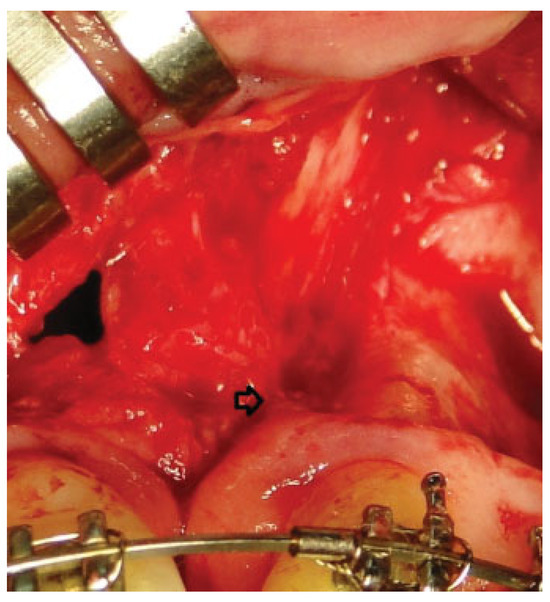

There were no intraoperative or postoperative complications. The fissure length in the upper edge when measured with a rule tool in the CBCT with Sirona Galileos software range from 5.76 to 16.93 mm (mean, 11.18 mm) (►Figure 4). All patients in the DBM group underwent a second CBCT assessment after 6 months of the surgical procedure. In the axial, coronal, and sagittal views and the three-dimensional reconstruction, there was no bone formation in none of the patients. The highest grayscale value in the area of the cleft was registered (►Figure 5), finding gray values between 1,148 and 1,496 (mean, 1,278.15). In our patients, the gray values corresponding to the bone adjacent to the cleft were higher than 1,504. During the follow-up performed 15 to 33 months postoperatively (mean, 28.2 months), occlusal and periapical X-ray were performed and analyzed by applying the Enemark scale; satisfying bone formation of 75% was observed only in just one patient. Four patients were reoperated with conventional surgery, using iliac crest grafts, because they need orthognathic surgery with Le Fort I osteotomy. At the time of reoperation, no bone formation was observed, although a crystallized material was seen in the pocket (►Figure 6) and was removed.

Figure 6.

The arrow shows crystallized material that was found in reoperations.